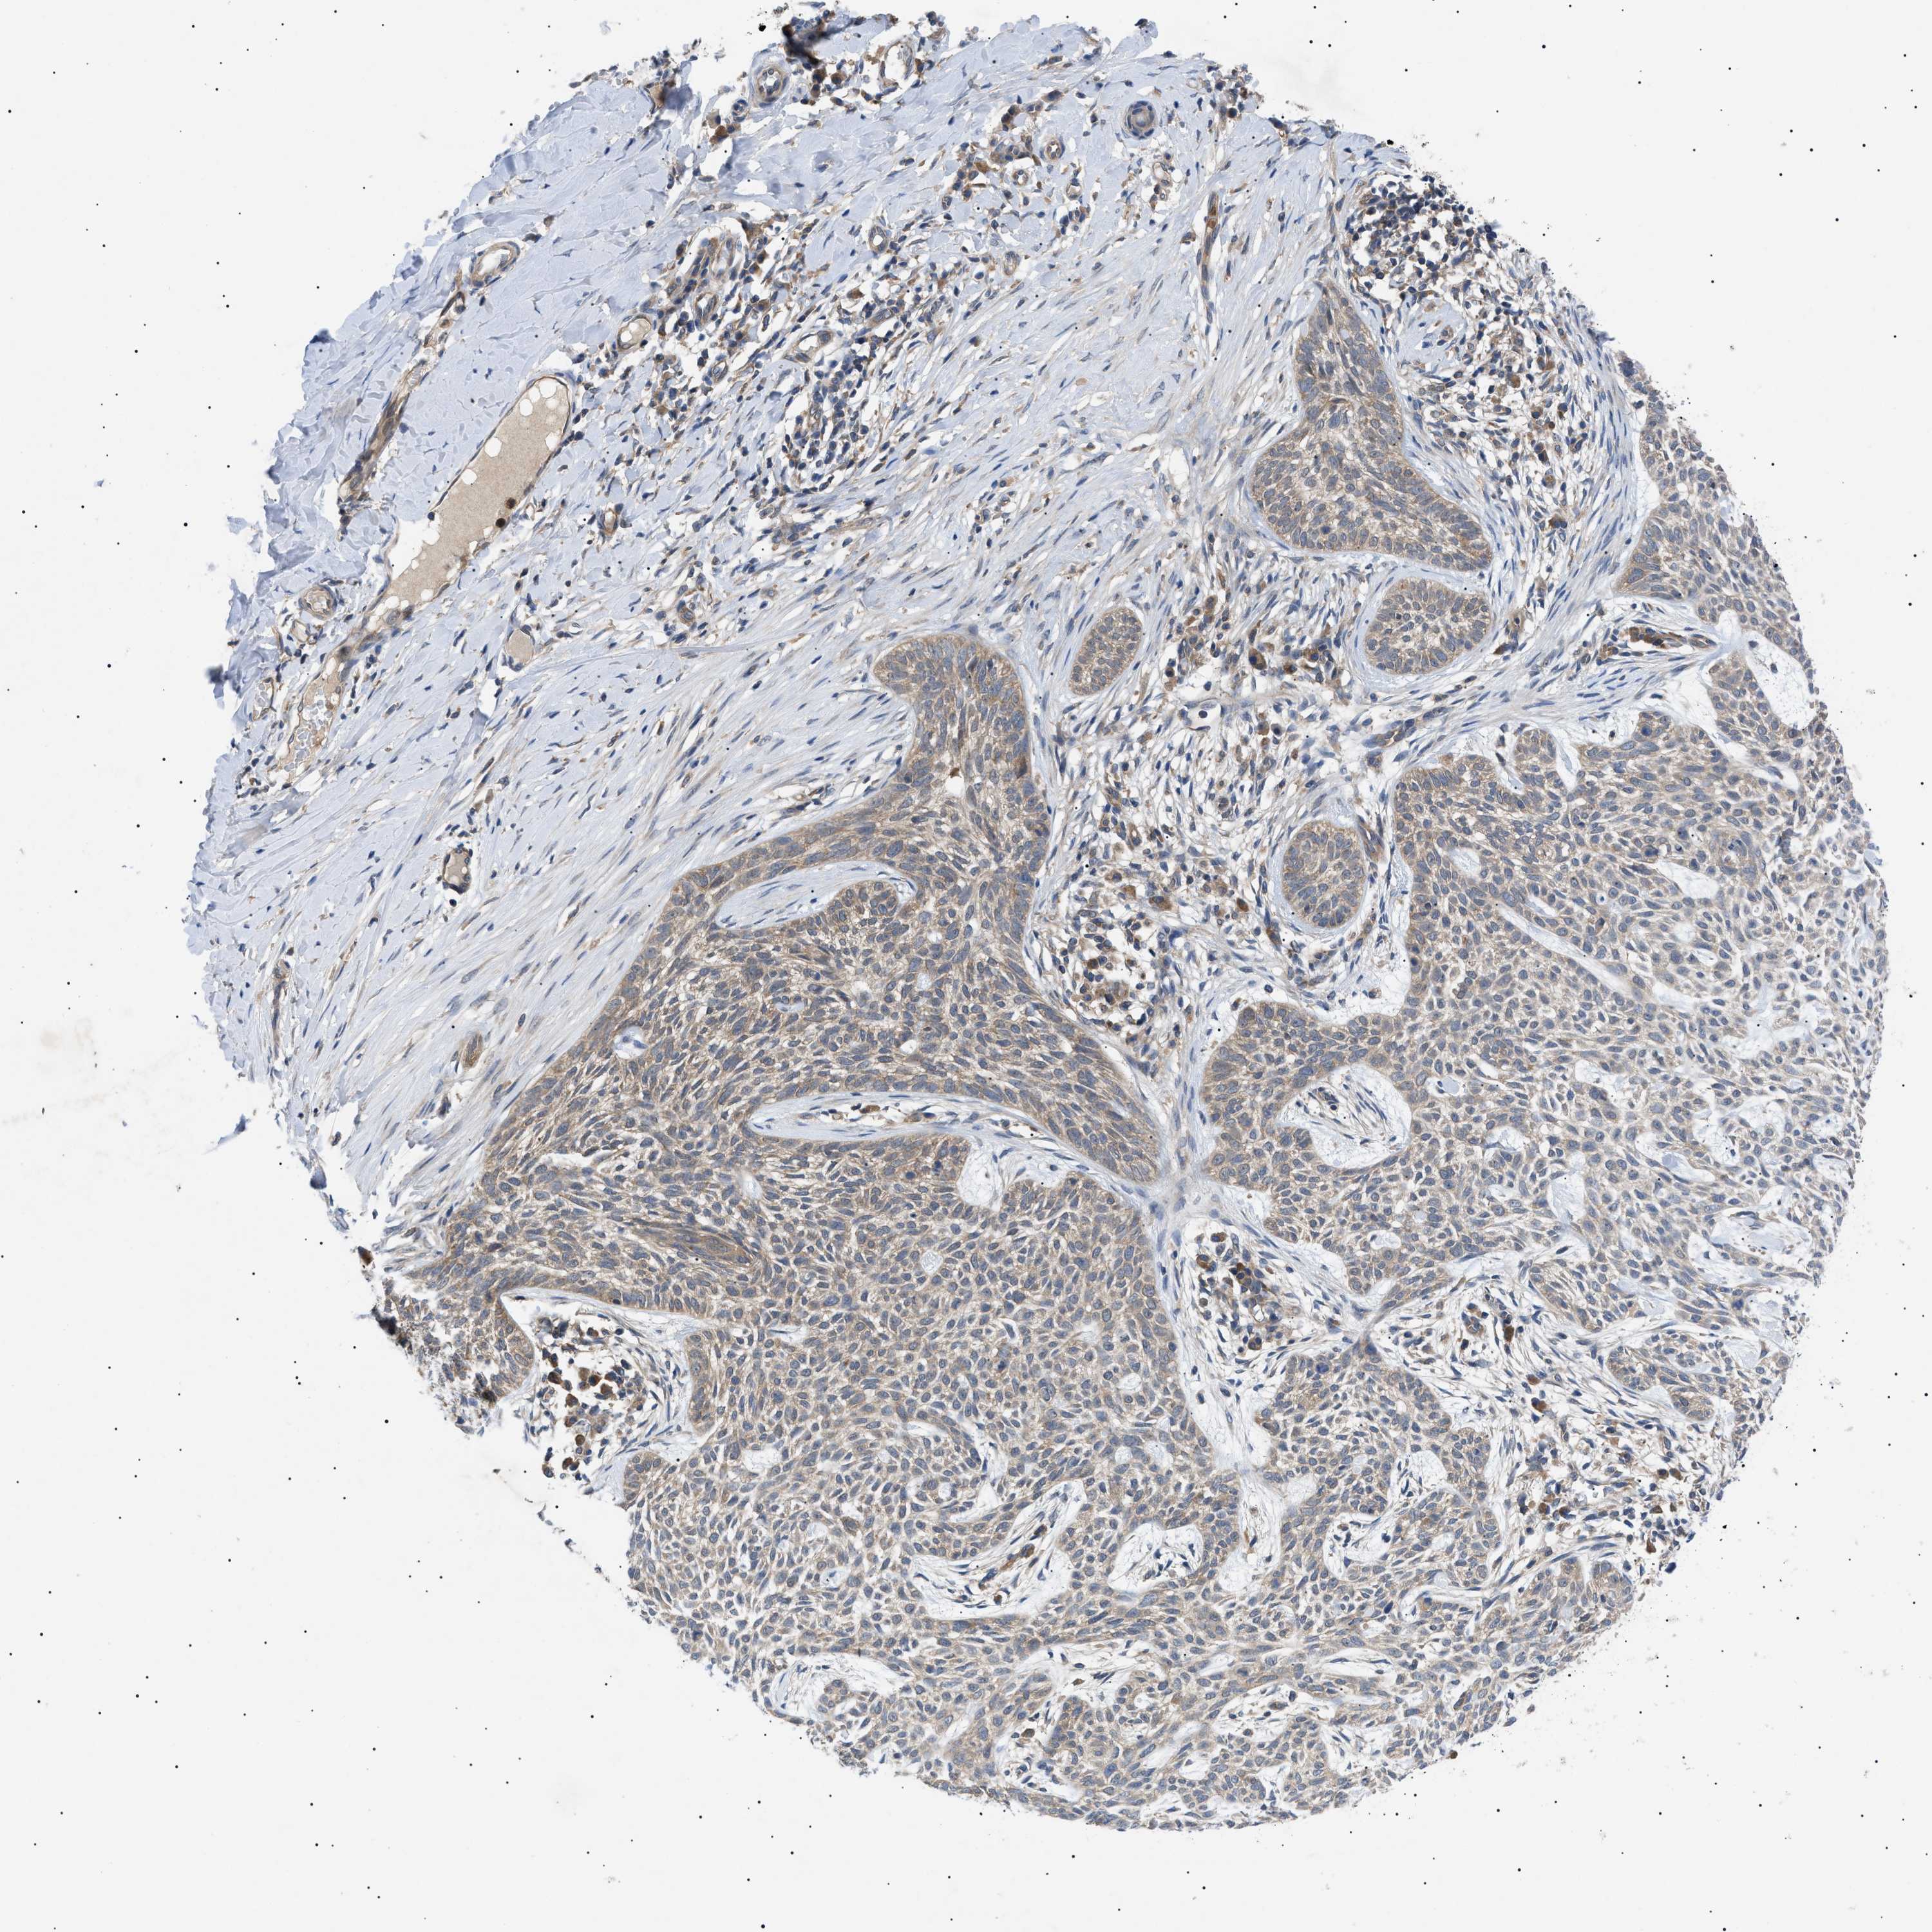

SKIN CANCER - Protein expressioni

A mouse-over function shows sample information and annotation data. Click on an image to view it in a full screen mode. Samples can be filtered based on level of antibody staining by selecting one or several of the following categories: high, medium, low and not detected. The assay and annotation is described here.

Each image is clickable and will lead to virtual microscopy that enables deeper exploration of all samples and also displays staining intensity scores, fraction scores and subcellular localization as well as patient and tissue information for each sample.

Antibody HPA015257

Squamous cell carcinoma in situ, NOS

Squamous cell carcinoma, NOS

Squamous cell carcinoma, metastatic, NOS

Basal cell carcinoma

Adnexal tumor, benign